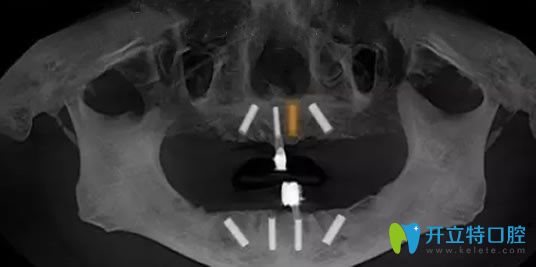

恢復(fù)了三個多月,經(jīng)過邱院長口腔檢查確認(rèn)無誤,就為老媽實施了ALL-on-4種植牙,利用四顆種植體為老媽種出整排牙齒,種植體的減少,避免了多次手術(shù),操作簡單,減少了手術(shù)創(chuàng)傷,手術(shù)時間短,種牙無需植骨,即種即用,讓老媽擁有了整齊潔白的牙齒,露出了燦爛的笑容。

寧波美萊口腔牙齒缺失種植牙恢復(fù)效果圖: